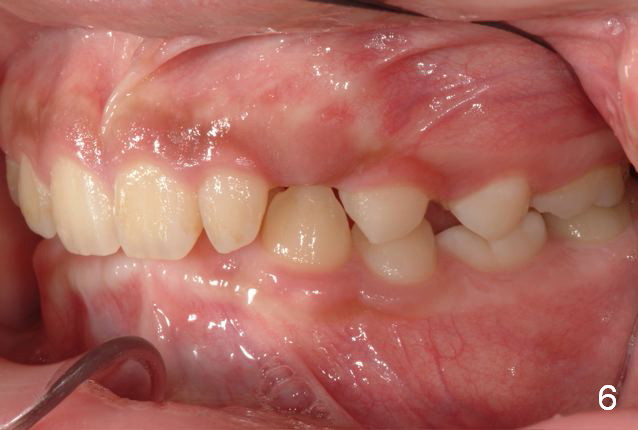

A 11-year-old boy has shorter lower 1/3 face (Fig.1,2) with light concave profile, especially the lower lip (Fig.3).  There is anterior deep bite (Fig.4) with Class II posterior occlusion (Fig.5,6).  UL2 is microdontia (Fig.7 *), while the Lower Es are retained (Fig.8).  Preop (2015_01_07) Ceph (Fig.9) and Pan (Fig.10) show ectopic L7s and congenitally missing L5s.